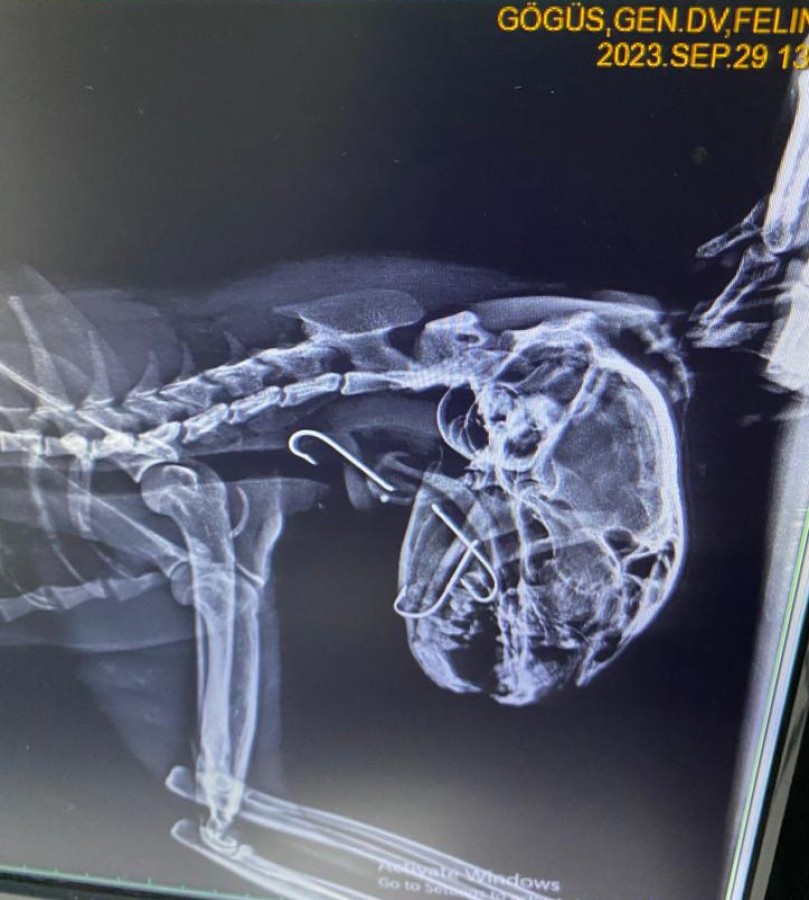

Veteriner hekime getirilen sokak kedisinin röntgeninde boğazına saplanmış üç tane olta kancası olduğu tespit edildi. Ameliyata alınan kedinin boğazındaki kancalar çıkartıldı. Yaklaşık bir saat süren ameliyatta kancaların derine saplandığı görüldü. Ameliyattan sonra kedi sağlığına kavuşurken veteriner hekim Furkan Alkan, süreci şöyle aktardı:

"Vaka geldiği zaman ağzında salya akıntısı ile geldi. Üç günden beri bu haldeymiş. İlk yaptığımız muayenede kancanın bir kısmını gördük ve hemen röntgeni çektik. Röntgende 3 tane kancanın boğazına takıldığını gördük. Endoskopi yardımıyla 3'ünü birden çıkardık. Üçü de çok derine saplanmıştı. Yarım saat bir saatlik bir operasyonla arkadaş sağlığına kavuştu. Ya balık alırken ya da balıkçılar tarafından atılan balığı kaparken kancayla beraber kaptı. Kancaları yuttu. Oraya saplandığı için de ne ağızda kaldı ne de mideye gitti. 3-4 günden beri enfeksiyonlu ağız akıntısı varmış, kliniğimize gelip tedavisini gördü. 4-5 yaşlarında sokak hayvanı. Bir hayvansever tarafından getirildi. Masraflarını hayvansever karşılıyor."